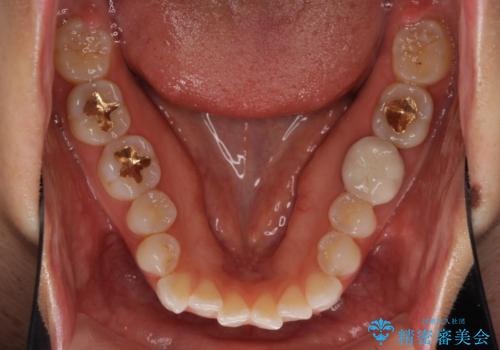

- 前歯のデコボコと上下スペースと前歯の隙間を気にして来院された患者様です。

目立たない装置を希望とのことでインビザラインにより、デコボコを解消しつつ、上下の前歯の隙間を閉じていくこととしました。

デコボコはあっという間に解消されましたが、上下前歯の隙間がなかなか解消されませんでした。

飲み込みの際に舌を前方に突出する癖があり、飲み込みの度に前歯に強く接触していたため、上下前歯の隙間が維持されていました。

舌の訓練を徹底していただいたことで、徐々に隙間は解消され、きれいな歯列に整えることができました。